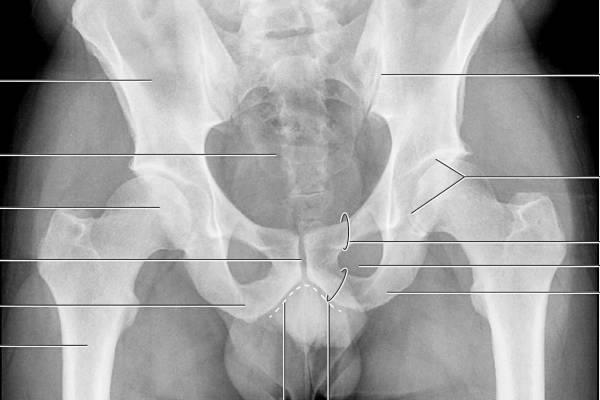

Как проводится диагностика заболевания

Предварительно диагноз часто ставится сразу, так как пациенты способны четко указать на место болей. Однако для окончательной диагностики требуется проведение специальных исследований, которые обычно включают:

- УЗИ позвоночника;

- Компьютерную и магнитно-резонансную томографию;

- Рентгенографию поясничной и крестцовой области;

- УЗИ органов брюшной полости.